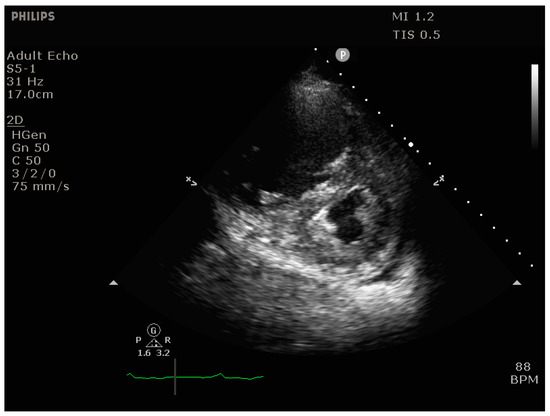

- Signs of RV dilation: D-shaping, increased RV:LV ratio, tricuspid regurgitation

- Signs of impaired RV systolic function: reduced tricuspid annular plane systolic excursion (TAPSE)

- Signs of elevated RV preload (plethoric inferior vena cava [IVC])